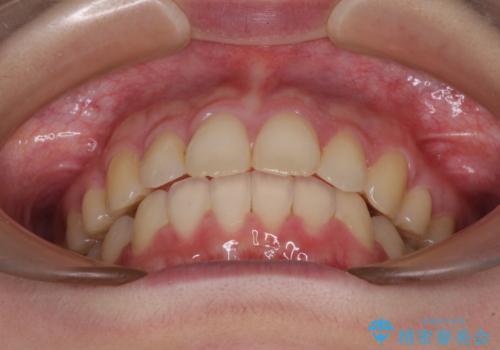

- 口元の突出感を気にして来院された患者様です。

左右ともに上顎奥歯が外を向き、下顎奥歯が内側に倒れているシザーズバイトであったため、補助装置により改善することとしました。

上下の咬み合わせは、下顎に対して上顎が相対的に前方にあったため、奥歯のシザーズバイト改善後に上顎左右第一小臼歯2本を抜歯し、上顎前突を改善していくこととしました。

左側の咬み合わせと上下正中の位置をコントロールするために時間がかかりましたが、事前に思い描いた通りの歯列に整い、患者様には大変満足していただきました。